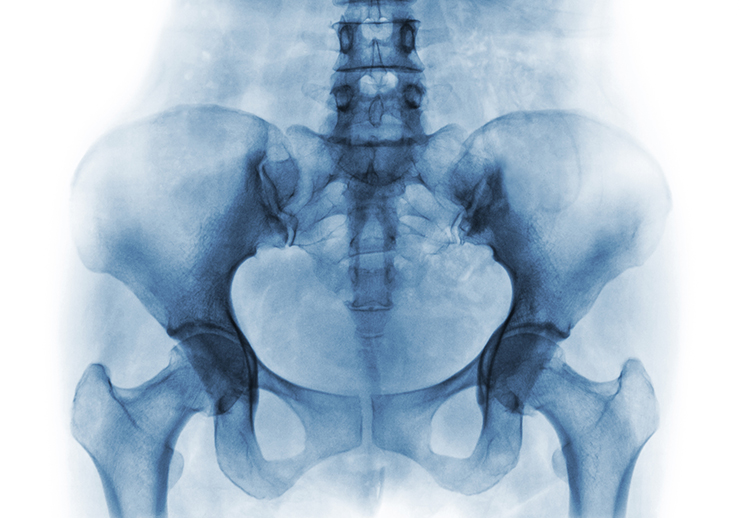

男性にも骨盤の病気がある!? MRI検査で調べよう

男性に起こる骨盤部の病気は、「前立腺炎」「前立腺がん」「骨腫瘍」「虫垂炎」「性感染症」「膀胱炎(尿路感染症)」「胃腸炎」などです。

男性にも女性と同様、定期的な骨盤の開閉が起こるといわれています。これが原因で骨盤や骨盤周辺の骨がゆがんで痛みが発生するケースもあるようです。また、骨盤そのものに骨腫瘍ができたり、間接や筋肉に炎症が起こったりしても痛みは発生します。さらには骨盤周辺の器官に炎症が起きても痛みが出るので、機能性の症状であるのか、あるいは病気を由来とする不調であるのか鑑別する診断が不可欠なのです。

骨盤周辺の軟部組織を調べる検査としては「MRI検査」がおすすめです。というのも、他の多くの画像検査は骨を透過しませんので、「見て」調べる検査項目は選択肢に限りがあります。

「MRI検査」は磁気共鳴を利用して体内を画像化する検査ですので、患者の身体に対する侵襲性がありません。骨盤や股関節、骨盤周辺の臓器、筋肉、血管などを同時に調べようと考えるのであれば、ぜひ「MRI検査」を選んでください。